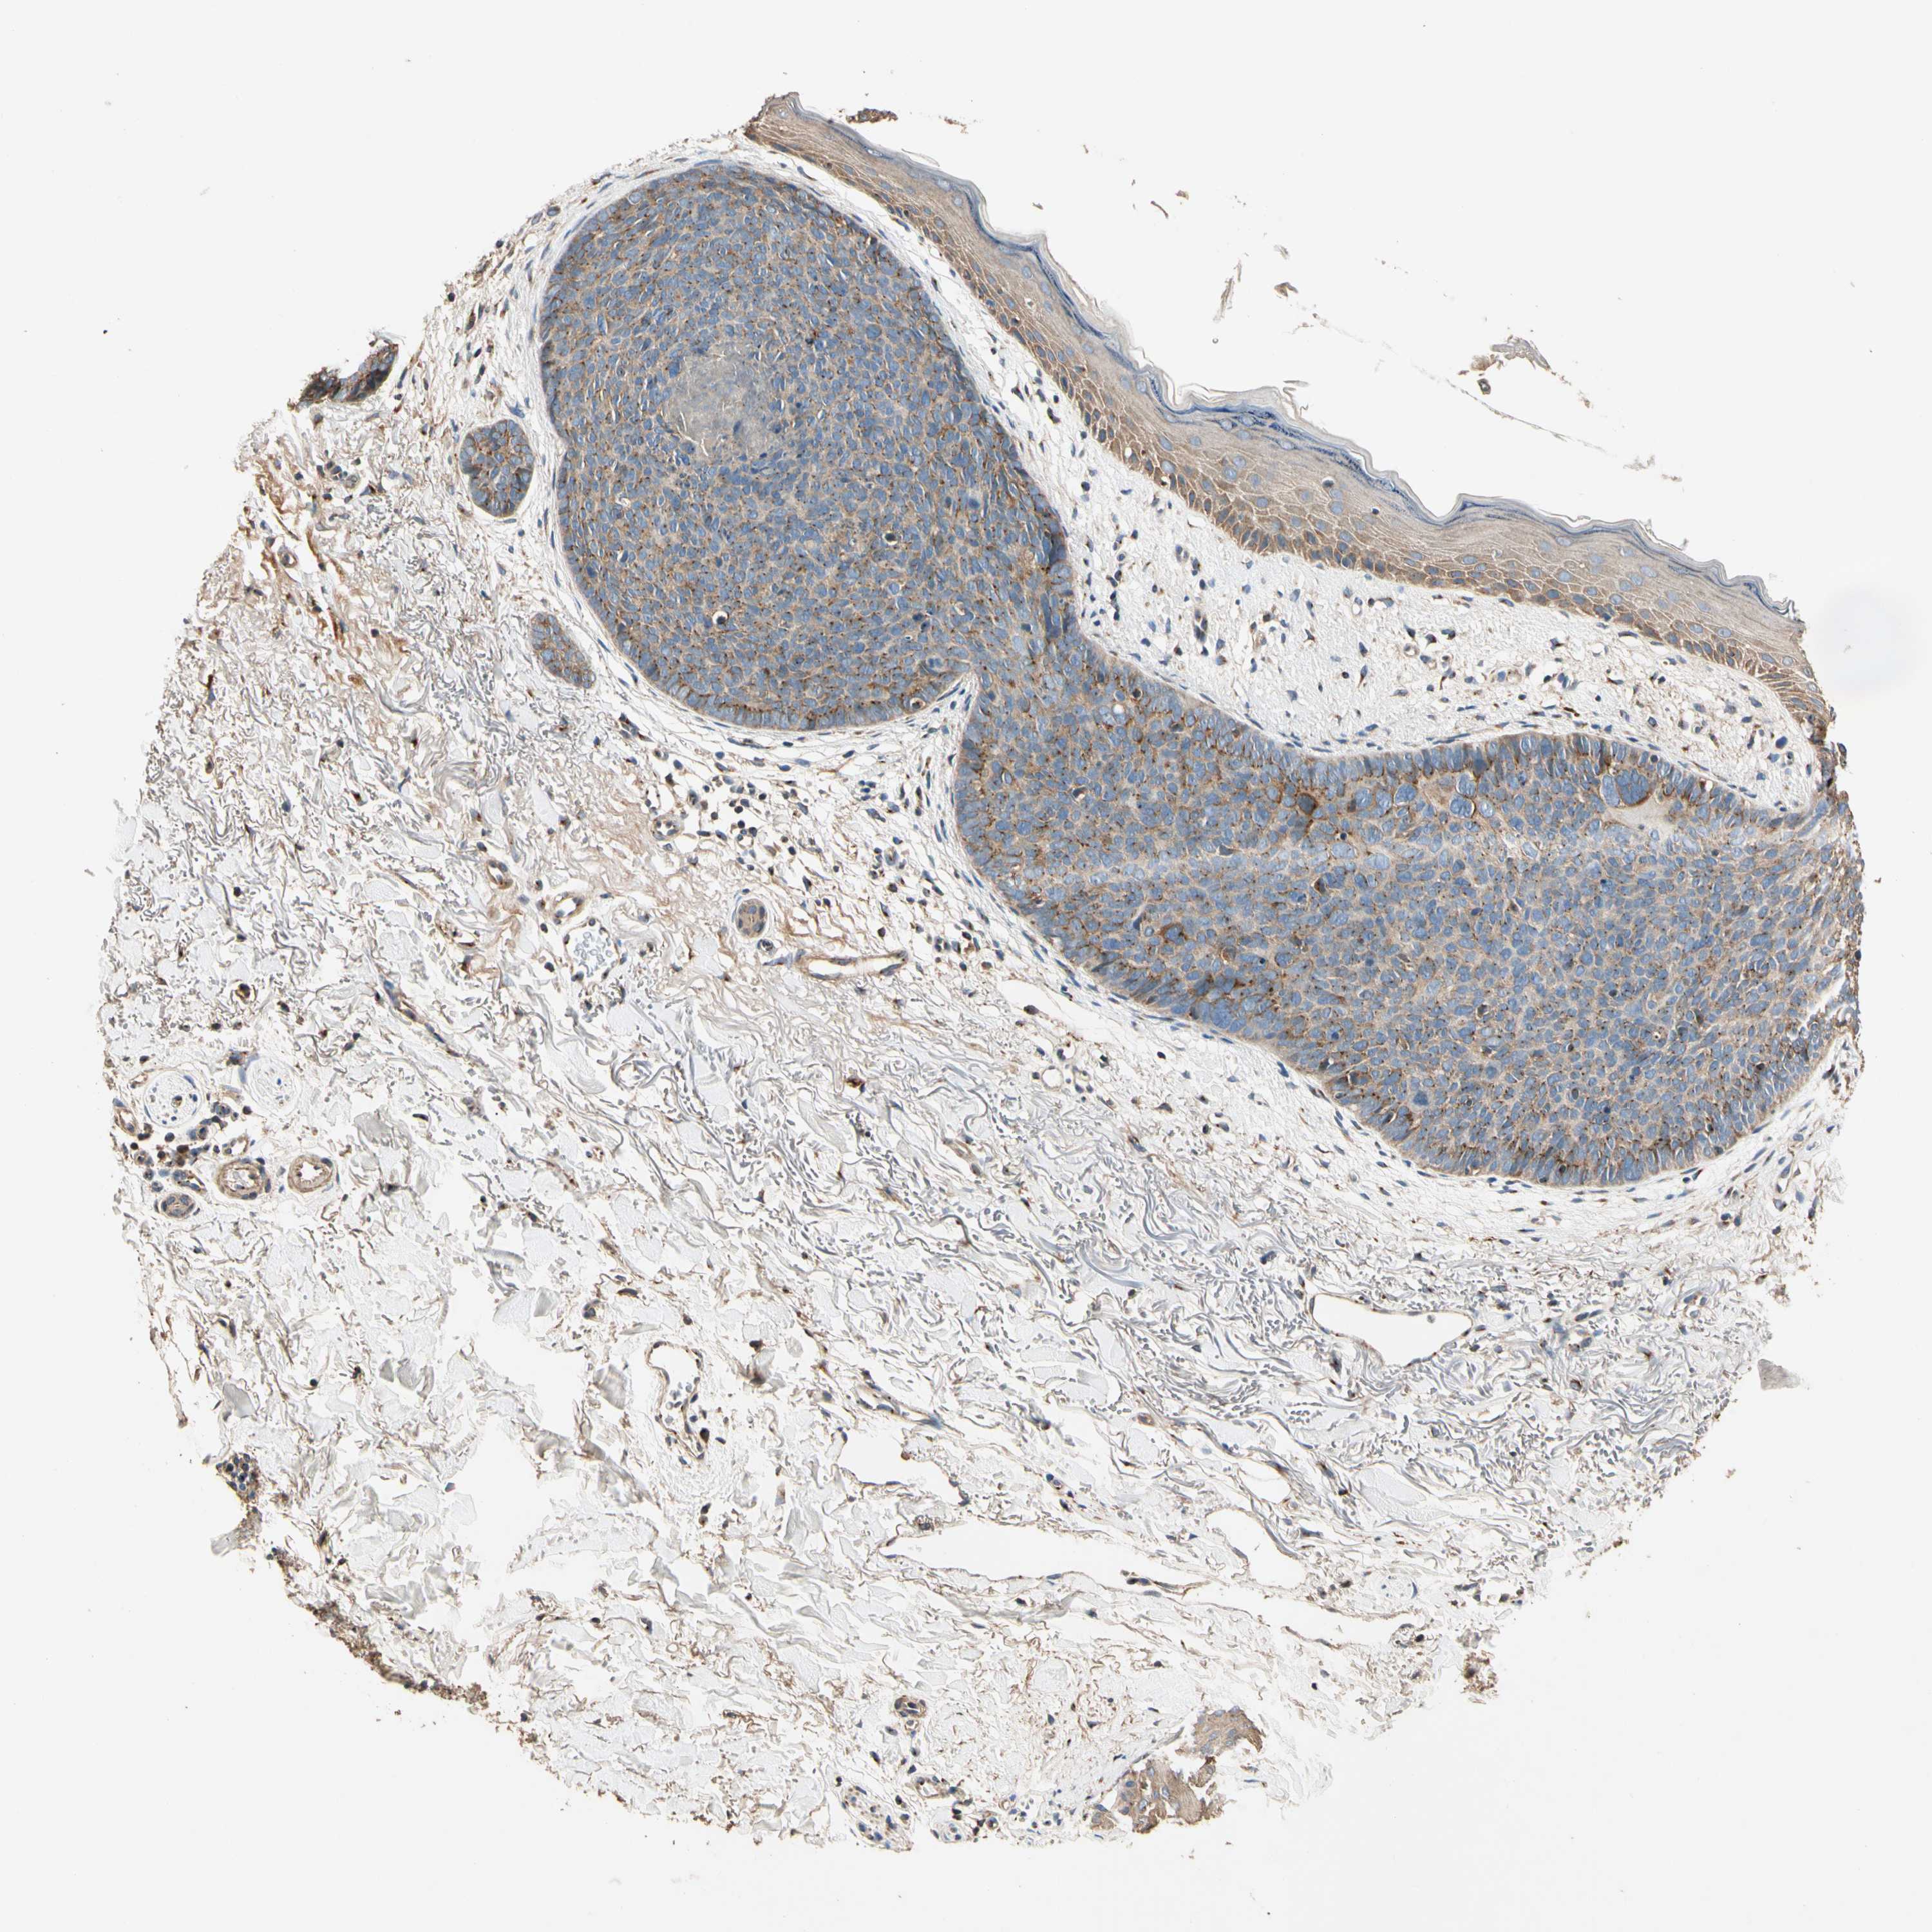

SKIN CANCER - Protein expressioni

A mouse-over function shows sample information and annotation data. Click on an image to view it in a full screen mode. Samples can be filtered based on level of antibody staining by selecting one or several of the following categories: high, medium, low and not detected. The assay and annotation is described here.

Antibody stainingi

Antibody staining in the annotated cell types in the current human tissue is reported as not detected, low, medium, or high, based on conventional immunohistochemistry profiling in selected tissues. This score is based on the combination of the staining intensity and fraction of stained cells.

Each image is clickable and will lead to virtual microscopy that enables deeper exploration of all samples and also displays staining intensity scores, fraction scores and subcellular localization as well as patient and tissue information for each sample.

Antibody HPA008548

Staining

High

Medium

Low

Not detected

Intensity

Strong

Moderate

Weak

Negative

Quantity

>75%

75%-25%

<25%

None

Location

Nuclear

Cytoplasmic/membranous

Cytoplasmic/membranous,nuclear

Squamous cell carcinoma, NOS